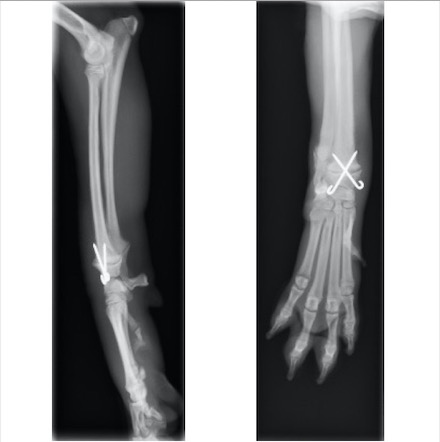

単純X線画像検査上、ラテラル像では大きな左右差は認められませんでしたが、AP像にて軟部組織の腫脹と成長板の間隙が広くなっていることから橈骨遠位成長板骨折(Salter-Haris Type1)と診断し、外科的処置を行いました。

初心時のX線画像検査初見 赤矢印:軟部組織の主張、黄矢印:橈骨遠位成長板(左前肢と比較すると成長板の間隙が広い)

キルシュナーワイヤーを用いたクロスピン法にて整復しました

術後約1ヵ月後 挙上が認められなくなり、負重をかけての歩行が可能になったため抜ピンを行いました